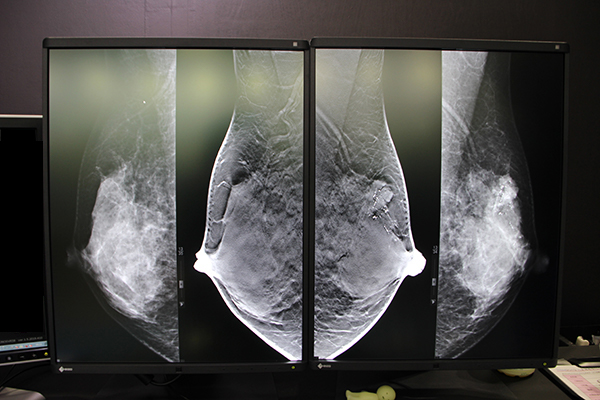

ブースでは各モニタメーカーの最新モニタでmammoditeのパフォーマンスを試すことができる。

ビューワは,独自開発の画像統合プロセスエンジン“APROS”を搭載し,高速な乳腺画像の表示スピードを実現。従来は表示までに時間がかかる,データ容量の多いトモシンセシスも含めたマンモグラフィ画像をウエイトタイムなしに表示することができ,読影へとスムーズに移行できる。今回ブースでは,新たに搭載されたディープラーニングを用いた独自症例で学習を行ったAIによる解析について説明が行われた。

mammoditeのビューワ。ウエイトタイムなしで表示することができる。